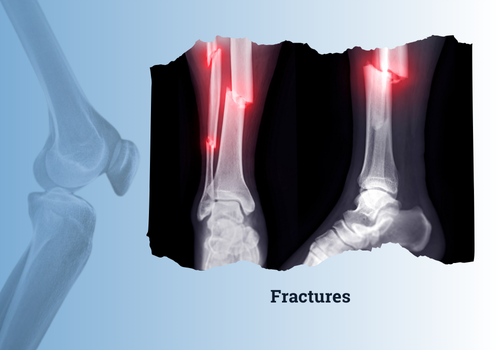

Fractures

A fracture refers to a break or crack in a bone caused by trauma, excessive force, or underlying medical conditions such as osteoporosis. Fractures can range from minor hairline cracks to severe breaks where the bone displaces or even pierces the skin (open fractures). Common symptoms include intense pain, swelling, bruising, and difficulty moving the affected area. Proper diagnosis through X-rays or imaging, along with appropriate treatment—whether through casting, splinting, or surgical intervention—is essential to ensure optimal healing, restore mobility, and prevent long-term complications such as misalignment or chronic pain.